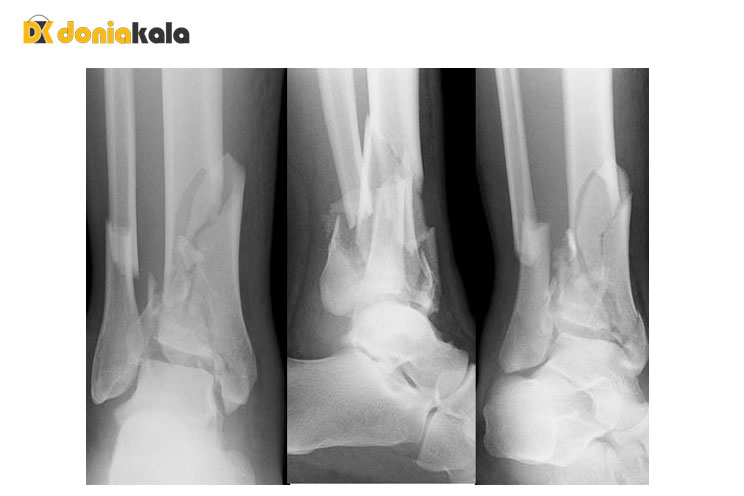

ارائه دهنده مراقبت های بهداشتی شما در مورد علائم و سابقه پزشکی شما با شما صحبت خواهد کرد. آنها یک معاینه فیزیکی کامل به شما خواهند داد تا شما را از نظر آسیب های دیگر بررسی کنند. ارائه دهنده شما همچنین ساق پا و مچ پا را به دقت بررسی می کند. آنها ممکن است به نواحی مختلف فشار وارد کنند تا ببینند که آیا در لمس دردناک هستند یا خیر، و ناحیه را از نظر تورم بررسی کنند. آنها همچنین مطمئن خواهند شد که خون رسانی به پا و مچ پا هنوز سالم است. ممکن است به عکس برداری با اشعه ایکس از پا، مچ پا و پای خود نیاز داشته باشید تا ببینید آیا استخوان های شما شکسته است یا خیر. همچنین ممکن است به سی تی اسکن نیاز داشته باشید تا آسیب خود را با جزئیات بیشتری ارزیابی کنید. یک ارائه دهنده مراقبت های بهداشتی اتاق اورژانس اغلب تشخیص شما را می دهد.